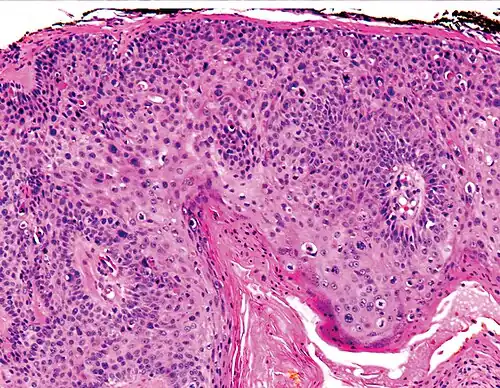

Degree of differentiation

-

Well-differentiated (yet invasive) cSCC, showing prominent keratinization. It may form pearl-like structures where dermal nests of keratinocytes attempt to mature in a layered fashion. Well-differentiated cSCC has slightly enlarged hyperchromatic nuclei with abundant amounts of cytoplasm. Intercellular bridges will frequently be visible.[12] -

Moderately differentiated lesions of invasive cSCC show much less organization and maturation with significantly less keratin formation.[12] -

Poorly differentiated, where attempts at keratinization are often no longer evident. This is a clear-cell squamous-cell carcinoma. The dysplastic cells infiltrated cords through the dermis. Poorly differentiated cSCC has greatly enlarged pleomorphic nuclei showing a high degree of atypia and frequent mitoses.[12] -

Poorly differentiated clear-cell squamous-cell carcinoma. For this type of cSCC, immunostains will likely be required to classify it unless other areas of the tumor show obvious squamous-cell features, such as seen here (arrow).